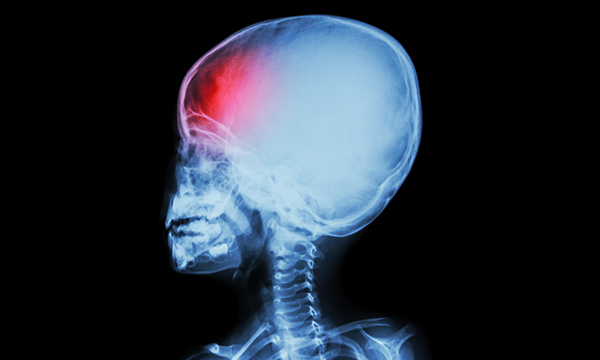

Caring for infants, children and young people with an acquired brain injury (ABI) can be challenging due to their developing brain and reliance on parents and caregivers. It is essential that children’s nurses are able to perform effective neurological observations, because these can identify deterioration and inform the management of patients with an ABI. This is the first of two articles that aim to encourage accuracy and consistency when undertaking neurological observations in infants, children and young people with an ABI to optimise their care. This first article details the pathophysiology, types and causes of ABIs and explains the potential complications that can occur following such injuries.